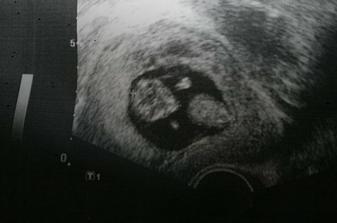

11.6.2009 1. UTZ kontrola, odpovídáme konci 6tt, srdíčko tluče!!!,

25.6.2009 miminko měří 14 mm, odpovídá 7+5, srdíčko ťukalo, takže krásně rosteme!